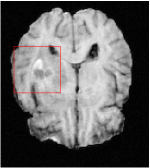

Qualitative comparison between conventional and Meta-learning methods are shown in Figure 1 and 3, which display the reconstructed MR images of the same slice for T1 and T2 respectively, we label the zoomed-in details of HGG in the red boxes. We observe the evidence that conventional learning is more blurry and lost sharp edges, especially in lower CS ratios. From the point-wise error map, we find meta-learning has the ability to reduce noises especially in some detailed and complicated regions comparing to conventional learning.

In general supervised learning, training data need to be in the same or similar distribution, heterogeneous data exhibits different structure variations of features which hinders CNNs to extract features efficiently. In our experiments, raw measurements sampled from different ratios of compressed sensing display different levels of incompleteness, these undersampled measurements do not fall in the same distribution but they are related. Different sampling masks are shown at the bottom of Figure 1 and 2 may have complemented sampled points, in the sense that some of the points which sampling ratio mask does not sample have been captured by other masks. In our experiment, different sampling masks provide their own information from their sampled points so that four reconstruction tasks help each other to achieve an efficient performance. Therefore, it explains the reason that Meta-learning is still superior to conventional learning when the sampling ratio is large.